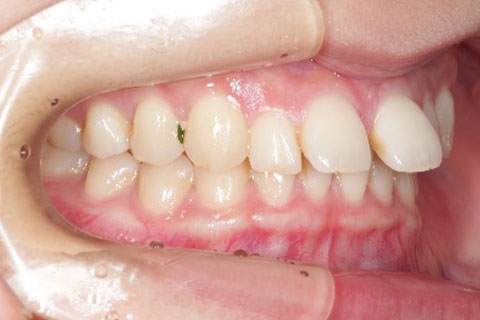

主訴:上下の歯並びのガタガタが気になる

診断名:上下顎叢生

症状:上下顎叢生

患者プロフィール:北九州市・小倉北区30代女性

治療方針:非抜歯治療

治療装置:マウスピース型矯正治療(インビザライン)

抜歯:無し

治療期間:一年半

通院回数:30回

リテーナー:上顎プレートタイプリテーナー 下顎フィクスタイプリテーナー

治療費用:検査診断料(20,000)+装置料金(500,000)+管理調整料(150,000) +装置撤去時診断料(10,000) +保定装置料金(20,000)=700,000(消費税込)

リスク副作用:痛み・治療後の後戻り・歯根吸収・歯髄壊死

詳しい症例説明:この患者さんはガタガタが気になり来院されました。マウスピースタイプの矯正装置で比較的短期間で治療を終えることができました。インビザライン(マウスピース矯正治療)で矯正治療を行うことで取り外して食事ができ、痛みもそれほど感じなかったとのことです。